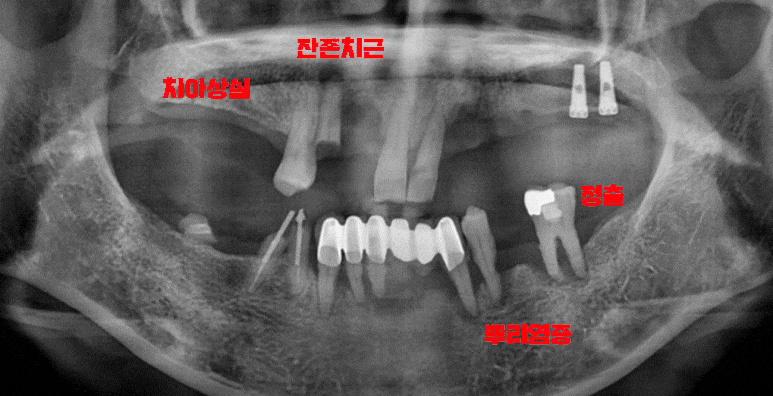

정확한 계획을 세우기 위해 정밀 검진을 진행했습니다.

이미 뿌리 염증이 심하게 퍼져있었기 때문에 더 이상 살릴 수 있는 치아는 없었습니다.

안타깝지만 어쩔 수 없이 전체임플란트 식립을 통해

잃어버린 기능과 외관을 살려줘야겠군요.

이수역 전체임플란트 식립 전